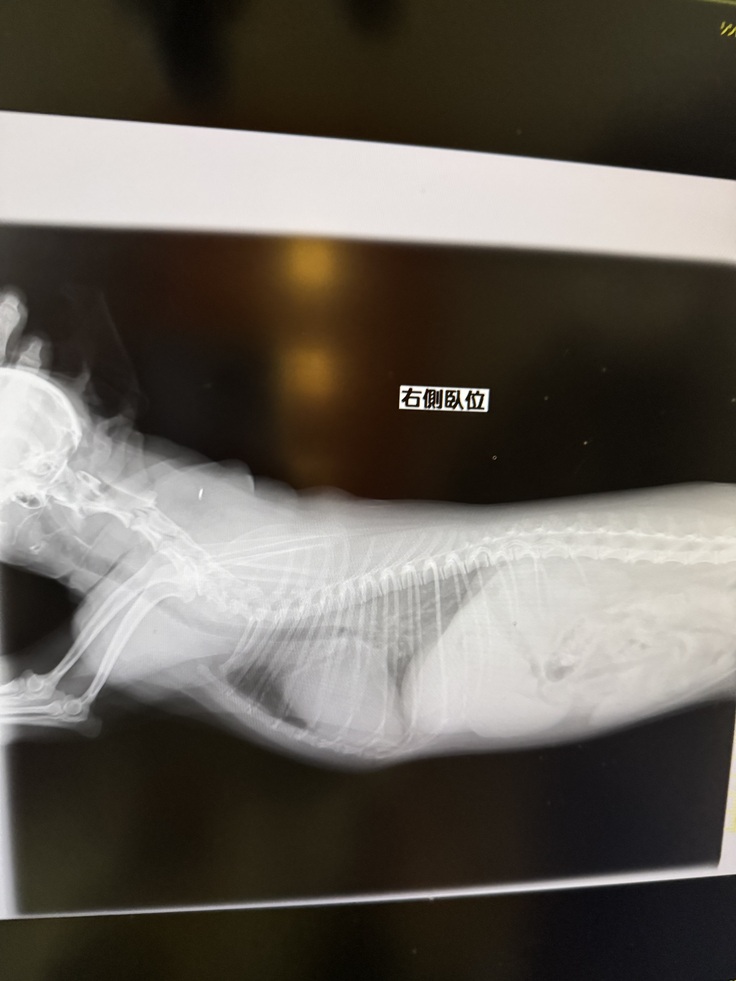

▶︎レントゲン写真(肺水腫の時の画像)

▶︎検査結果

▶︎数日後のレントゲン写真(左が数日後 右が肺水腫の時)

この時主治医からは、

ステージBからステージCに急になりましたと告げられました。

▶︎レントゲン写真

心臓が大きく、肥大してしまってます。

▶︎二度目の肺水腫のレントゲン画像

左側肺水腫 右側正常な時

左側の上の部分が右側より白くなっています。